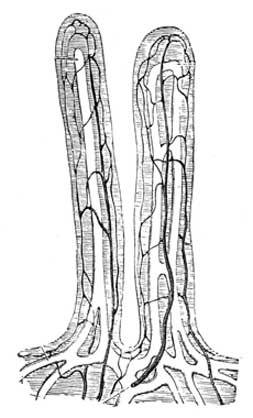

Fig. 2.—Two villi containing lacteals. The white canals are lacteals, the darker lines indicate blood vessels (capillaries). Magnified 100 diameters.

(From "Quain's Anatomy.")

Interior of small intestine.